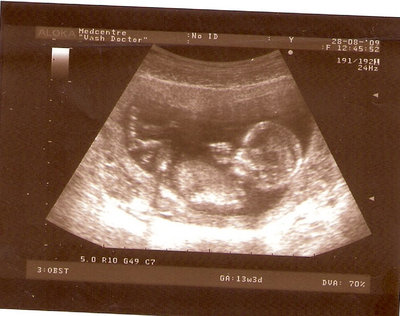

13 НЕД И 5 ДНЕЙ

| Вложения: |

3.jpg [ 96.81 КБ | Просмотров: 2448 ]

Nikisa писал(а): Foto prosto chudesnoe. A na kakom sroke uznali, chto sin.............. НА 13 НЕДЕЛЯХ.КАК РАЗ ВОТ В ЭТО узи, ОНО УМЕНЯ ВТОРОЕ БЫЛО. ЭТО КОНЕЧНО МАЛЕНЬКИЙ СРОК ДЛЯ ОПРЕДЕЛЕНИЯ ПОЛА. НО Я ПОПРОСИЛА ВРАЧА(ЭТО КТСТАТИВ РОССИИ БЫЛО) ХОТЯ БЫ ПРЕДПОЛОЖИТЬ. ЕЙ ВСЁ ТАКИ УДАЛОСЬ РАССМОТРЕТЬ.НУ ВООБЩЕМ ЧЕРЕЗ НЕСКОЛЬ ДНЕЙ ПОЙДУ К ВРАЧУ, УЖЕ АМЕРЕКАНСКОМУ И УЗНАЮ ТОЧНО. К ТОМУ ВРЕМЕНИ У МЕНЯ БУДЕТ СРОК 18 НЕДЕЛЬ. ХОТЕЛОСЬ БЫ ПОСМОТРЕТЬ НА ДРУГИЕ ФОТО НА ЭТОМ СРОКЕ ИЛИ БОЛЬШЕ. ТАК ЧТО ВЫКЛАДЫВАЙТЕ, ЕСЛИ НЕ ЖАЛКО!